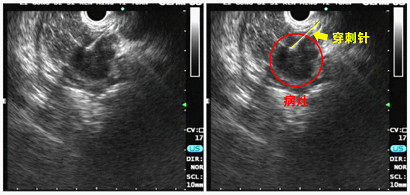

超声内镜是指将内镜镜身前端与超声探头结合运用,对消化道和邻近器官进行近距离的扫描,实时传回高分辨率的超声图像。相比于传统的内窥镜检查及体表超声检查,超声内镜不受消化道气体、脂肪和骨骼的干扰,更加贴近病变局部以发现局部病变,其敏感度可高达97%,特别在诊断直径<2cm的胰腺癌时敏感性高于CT。因此,超声内镜被认为是目前胰腺癌检查与分期最敏感的技术。

超声内镜的另一优点是对局部淋巴结转移和血管侵犯的准确性较高,能通过细针穿刺(FNA)获得组织病理学的金标准诊断。所以做个超声内镜完全有可能更好更早地发现早期胰腺癌。